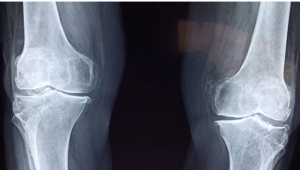

🦵 X-Ray Knee at Surya Diagnostics Center, Nanded City, Pune

Accurate Imaging for Knee Pain, Injury, and Joint Disorders

At Surya Diagnostics Center, Nanded City, Pune, we specialize in providing accurate, safe, and fast diagnostic imaging to help patients get the right treatment at the right time. One of our most frequently performed and essential imaging procedures is the X-Ray of the Knee Joint, used to diagnose pain, injuries, arthritis, and other knee-related conditions.

An X-Ray Knee is a simple and non-invasive imaging test that uses a small amount of radiation to create clear pictures of the bones in the knee joint, including the femur (thigh bone), tibia (shin bone), fibula, and patella (kneecap).